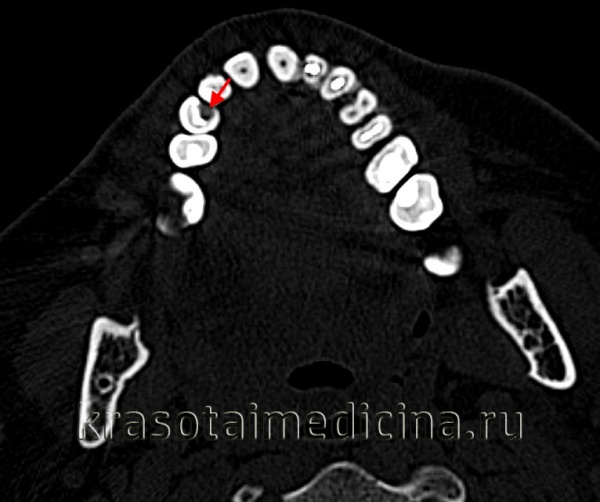

Диагностируют кариес во время визуального и инструментального осмотров стоматолога. Субъективные ощущения пациента позволяют судить о глубине процесса, но не являются основными диагностическими критериями. В процессе диагностики проводится прицельная рентгенография зуба, электроодонтометрия.

- Рентгенологическое исследование. Пациенту выполняется внутриротовой прицельный снимок одного или двух-трех больных зубов. На нем хорошо визуализируются размеры и глубина очага, что позволяет оценить целостность границы между дентином и цементом. Особое внимание уделяется расстоянию от дна кариозной полости до пульпарной камеры.